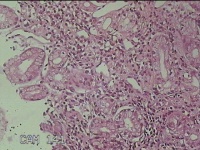

胃角粘膜

性别

男

年龄

29岁

临床诊断

复合性溃疡;慢性胃炎

一般病史

上腹部疼痛1个月余。

标本名称

大体所见

灰白粉红色组织小米大2团。

图1

良性病变。